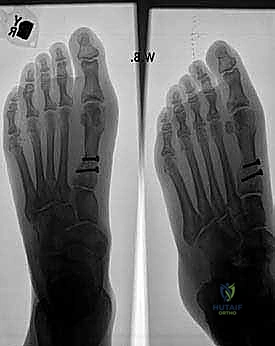

FIG 2 • A–D. Preoperative and postoperative radiographs.